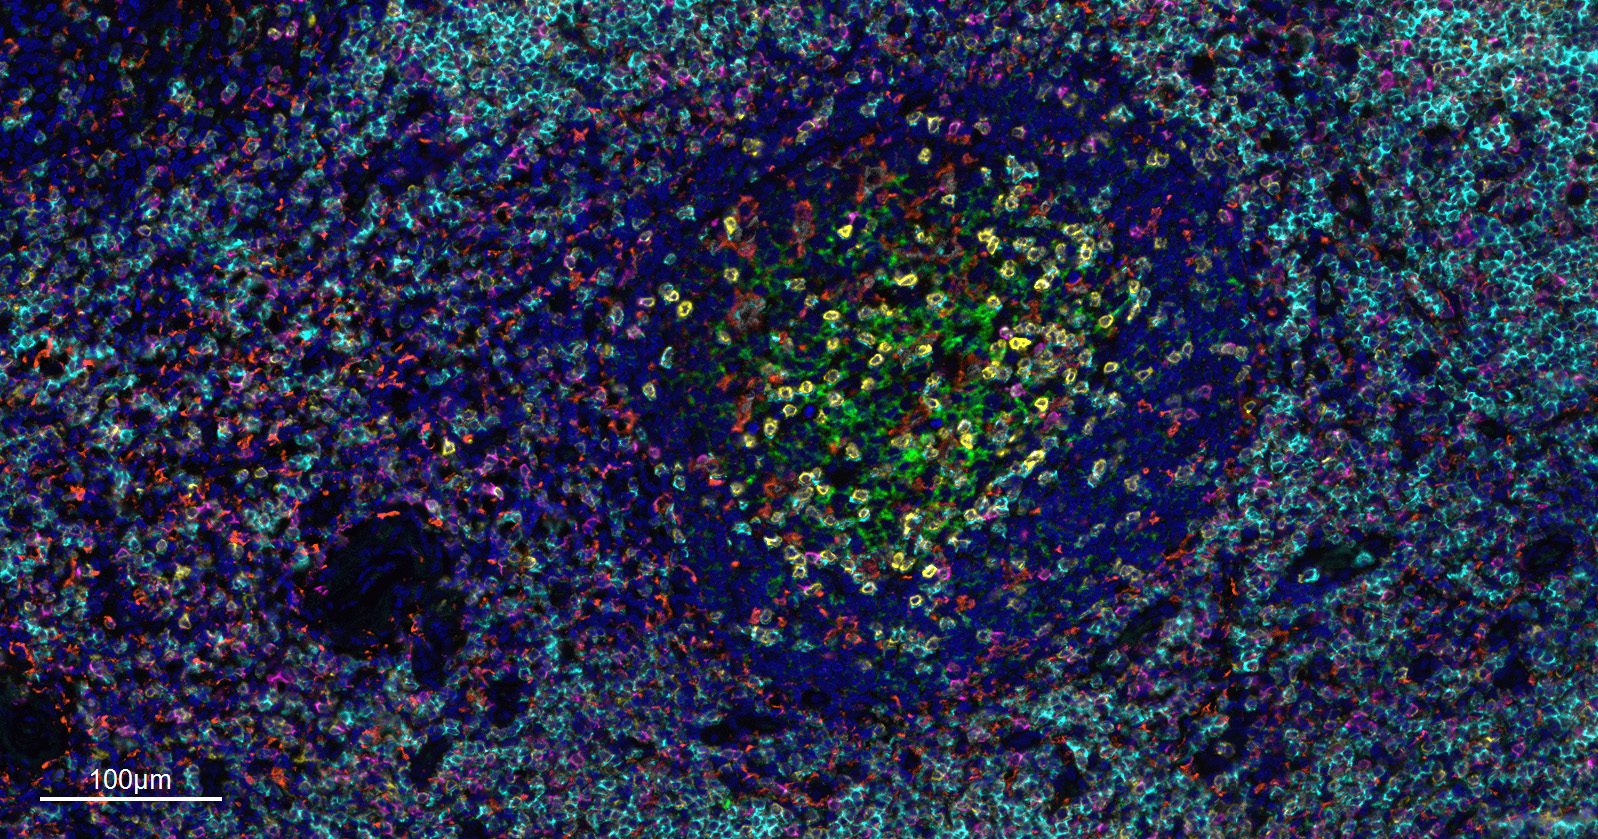

| IF |

1:200-1000 |